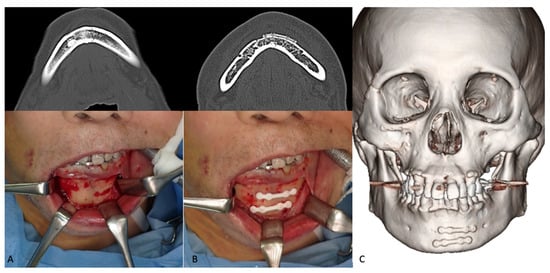

3.1.3. Mandibular Fractures

3.2.2. Mandibular Osteotomies